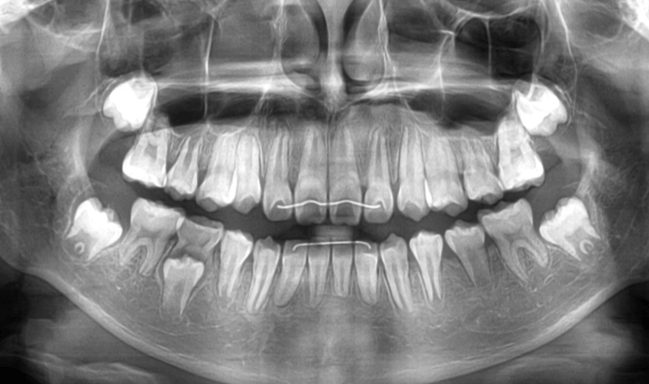

| 年齢・性別 | 7歳1ヶ月の男児 |

|---|---|

| 主訴 | 歯の生えるスペース不足が懸念され、歯列の乱れ(叢生)を整えるために来院された患者様です。 |

| 治療期間・回数 | 1年3ヶ月・11回 |

| 費用 | 420,000円(税別) |